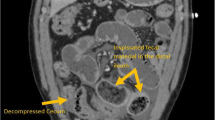

CF is associated with many gastrointestinal manifestations (Fig. 1). Effects of CFTR dysfunction on the digestive system are evident early and feature prominently. CF mouse models display poor growth and potentially lethal bowel obstruction [5]. CF may present in infancy with gastrointestinal obstruction (meconium ileus), poor digestive function due to inability to neutralize gastric acid, and exocrine pancreatic insufficiency (EPI) leading to nutritional deficiencies and failure to thrive. About 85% of the CF population develops EPI during the first year of life [6]. Pancreatic sufficient patients are at risk for pancreatitis. Although endocrine pancreatic function is relatively preserved early in life, the gradual destruction of islet cells in many patients with CF leads to a high prevalence of cystic fibrosis-related diabetes (CFRD) in adults. Gastroesophageal reflux, constipation, gastroparesis, cholelithiasis, and small intestinal bacterial overgrowth are common. Potentially life-threatening complications include liver disease and distal intestinal obstruction syndrome (DIOS), in which inspissated stool in the ileocecum leads to bowel obstruction. CF patients have an increased risk for gastrointestinal cancers [7] as detailed below.

Potential impact of Cystic Fibrosis Transmembrane Conductance Regulator (CFTR) modulators on gastrointestinal manifestations of cystic fibrosis (CF). The boxed panel on the left highlights gastrointestinal complications of cystic fibrosis, grouped primarily by organ. The inset graphic in the lower right represents alterations in the fecal microbiome (dysbiosis). Inhibitory arrows (dashed because they are predominantly theoretical at this time) represent potential effects of CFTR modulators on gastrointestinal symptoms, dysbiosis, and other gastrointestinal complications of CF. GI, Gastrointestinal

The purpose of this review is to highlight topics of current importance in the gastroenterological realm of CF. While not exhaustive, the following topics encompass important recent scholarship or emerging therapies. We will discuss the assessment of GI-specific symptom questionnaires and scoring systems in CF, followed by the potential role of intestinal dysbiosis in GI manifestations of CF. Recent screening recommendations address the increased risk of colon cancer in CF, which likely results in part from intestinal dysbiosis. We will conclude with a discussion of CFTR modulators and their potential role in altering GI symptoms or complications in CF. Figure 1 depicts the themes covered in this literature review and their potential interdependence.

We thank Sarah Kathryn Stevens for her work as medical illustrator for Figure 1 and the University Hospitals Cleveland Medical Center Department of Surgery for her salary support.